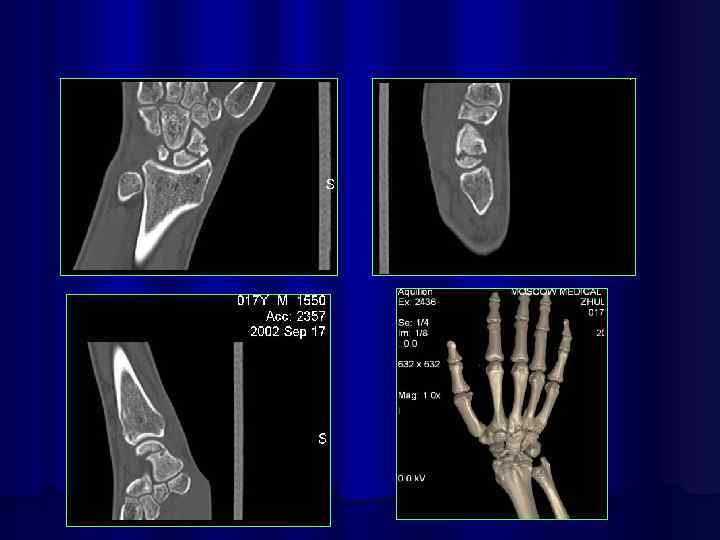

4 -d реконструкция костей лицевого черепа

4 -d реконструкция кисти и стопы

3 -d реконструкция изображений на 64 срезовом спиральном КТ